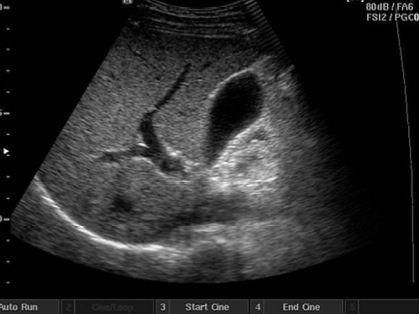

nl galbladder

Acute cholecystitis

Gallstones